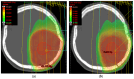

Glioblastoma, the most aggressive and common malignant primary brain tumour, is characterized by infiltrative growth, abundant vascularization, and aggressive clinical evolution. Patients with glioblastoma often face poor prognoses, with a median survival of approximately 15 months. Technological progress and the subsequent improvement in understanding the pathophysiology of these tumours have not translated into significant achievements in therapies or survival outcomes for patients. Progress in molecular profiling has yielded new omics data for a more refined classification of glioblastoma. Several typical genetic and epigenetic alterations in glioblastoma include mutations in genes regulating receptor tyrosine kinase (RTK)/rat sarcoma (RAS)/phosphoinositide 3-kinase (PI3K), p53, and retinoblastoma protein (RB) signalling, as well as mutation of isocitrate dehydrogenase (IDH), methylation of O6-methylguanine-DNA methyltransferase (MGMT), amplification of epidermal growth factor receptor vIII, and codeletion of 1p/19q. Certain microRNAs, such as miR-10b and miR-21, have also been identified as prognostic biomarkers. Effective treatment options for glioblastoma are limited. Surgery, radiotherapy, and alkylating agent chemotherapy remain the primary pillars of treatment. Only promoter methylation of the gene MGMT predicts the benefit from alkylating chemotherapy with temozolomide and it guides the choice of first-line treatment in elderly patients. Several targeted strategies based on tumour-intrinsic dominant signalling pathways and antigenic tumour profiles are under investigation in clinical trials. This review explores the potential genetic and epigenetic biomarkers that could be deployed as analytical tools in the diagnosis and prognostication of glioblastoma. Recent clinical advancements in treating glioblastoma are also discussed, along with the potential of liquid biopsies to advance personalized medicine in the field of glioblastoma, highlighting the challenges and promises for the future.